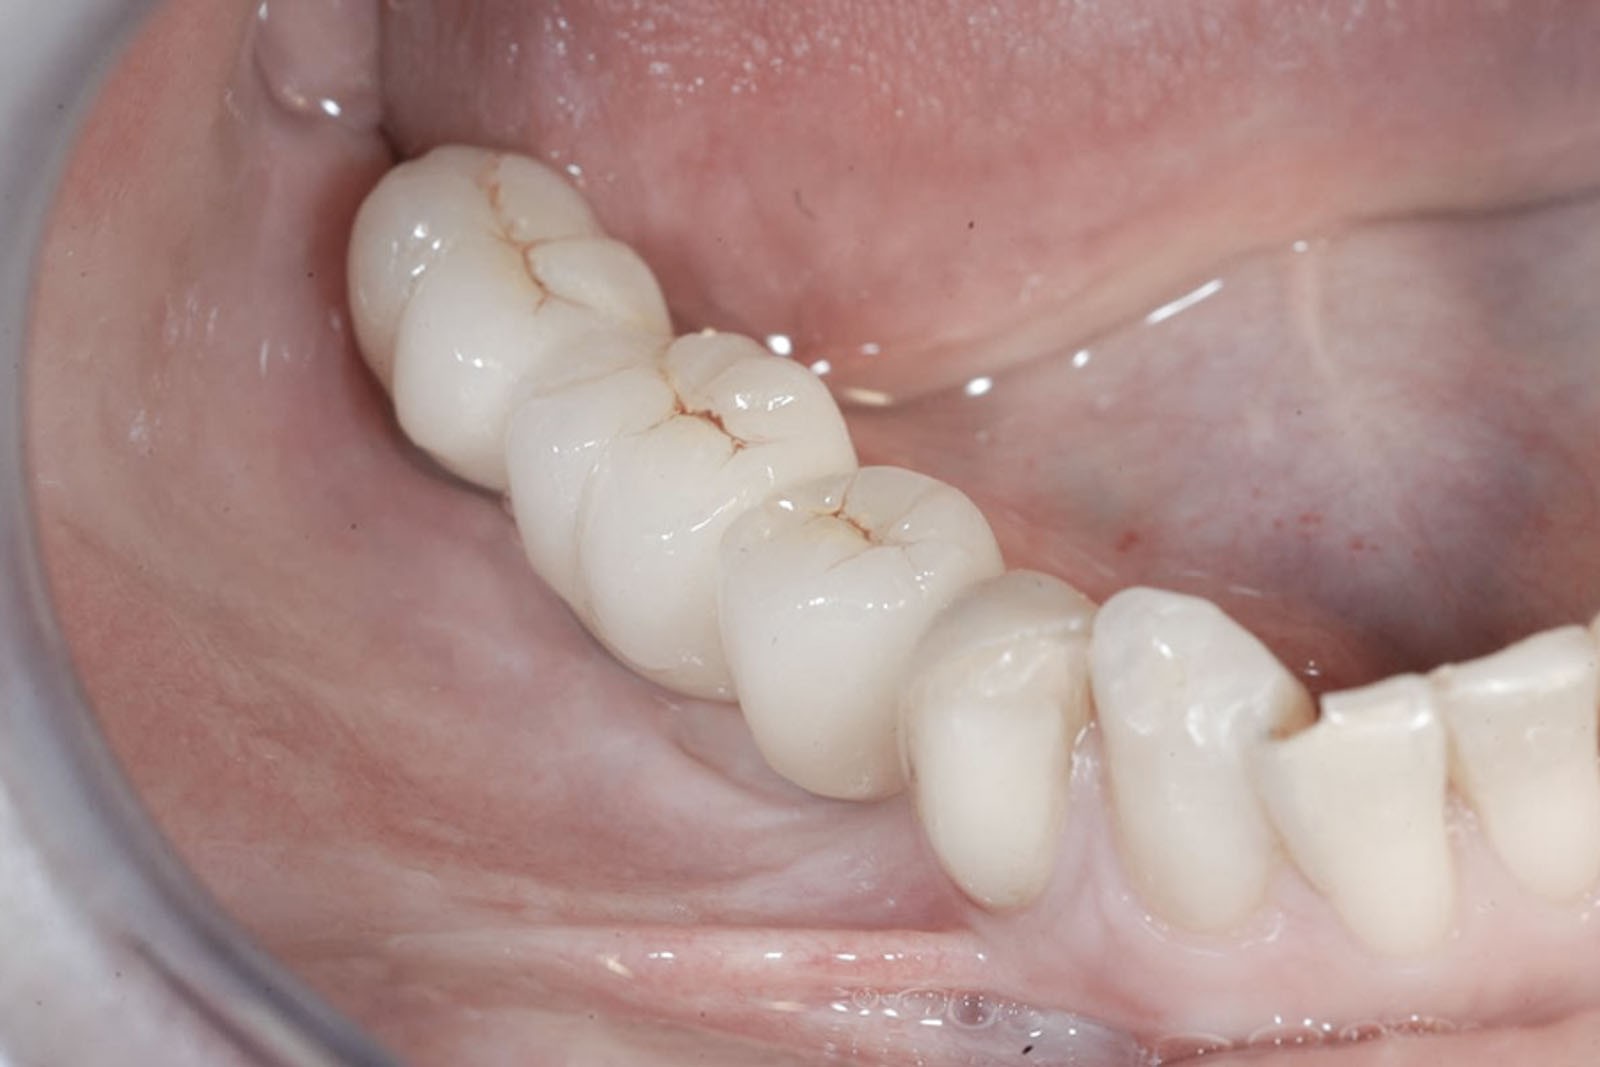

Zabieg odbudowy zębodołu powinno się wykonać możliwe jak najszybciej po usunięciu zęba. Jego celem jest odbudowa naturalnej objętości kości w miejscu utraconego zęba, a następnie szybkie wprowadzenie implantu. Najlepsze rezultaty uzyskuje się przy zastosowaniu biomateriału w formie bloczków kolagenowych lub granulatu, które dają trwałe efekty odbudowy oraz optymalną funkcję i estetykę odtworzonych koron zębów na wszczepionym implancie.

Metoda rekonstrukcji kostnej w oparciu o indywidualnie drukowane siatki z tytanu dla implantacji wszczepów śródkostnych stosowana jest najczęściej jako dwuetapowa. W pierwszym etapie odbudowywana jest kość, natomiast implanty wszczepiane są po okresie 4–6 miesięcy. Na wgojenie implantów oczekujemy od 4 do 6 miesięcy w zależności od miejsca ich lokalizacji. Siatka tytanowa po spełnieniu swojej funkcji rusztowania dla odbudowującej się kości jest następnie usuwana w dniu wszczepienia implantu. Jeżeli kość spełnia odpowiednie warunki, istnieje możliwość zastosowania modyfikacji siatki tytanowej, która umożliwia jednoczesne wprowadzenie implantów wraz z odbudową kostną. Wariant ten skraca czas od pierwszego zabiegu do wykonania gotowych koron protetycznych na wprowadzonych implantach.